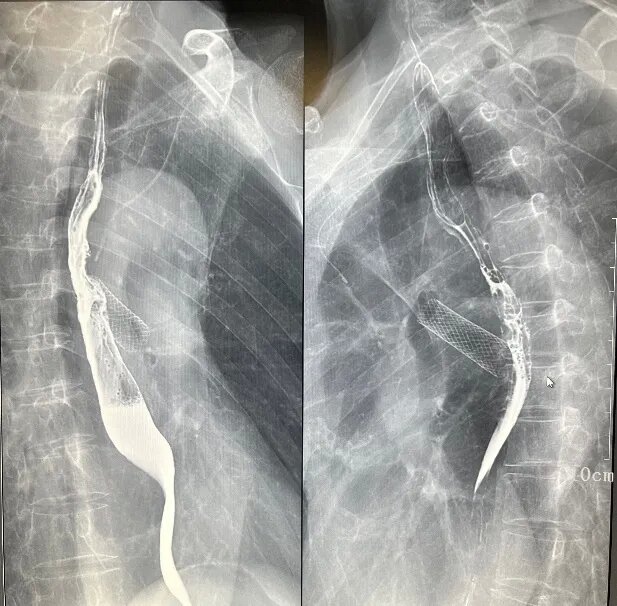

(一)食道鋇劑造影

三、介入診療

如膽道造影、T管造影、ERCP,支持簡單的介入治療。